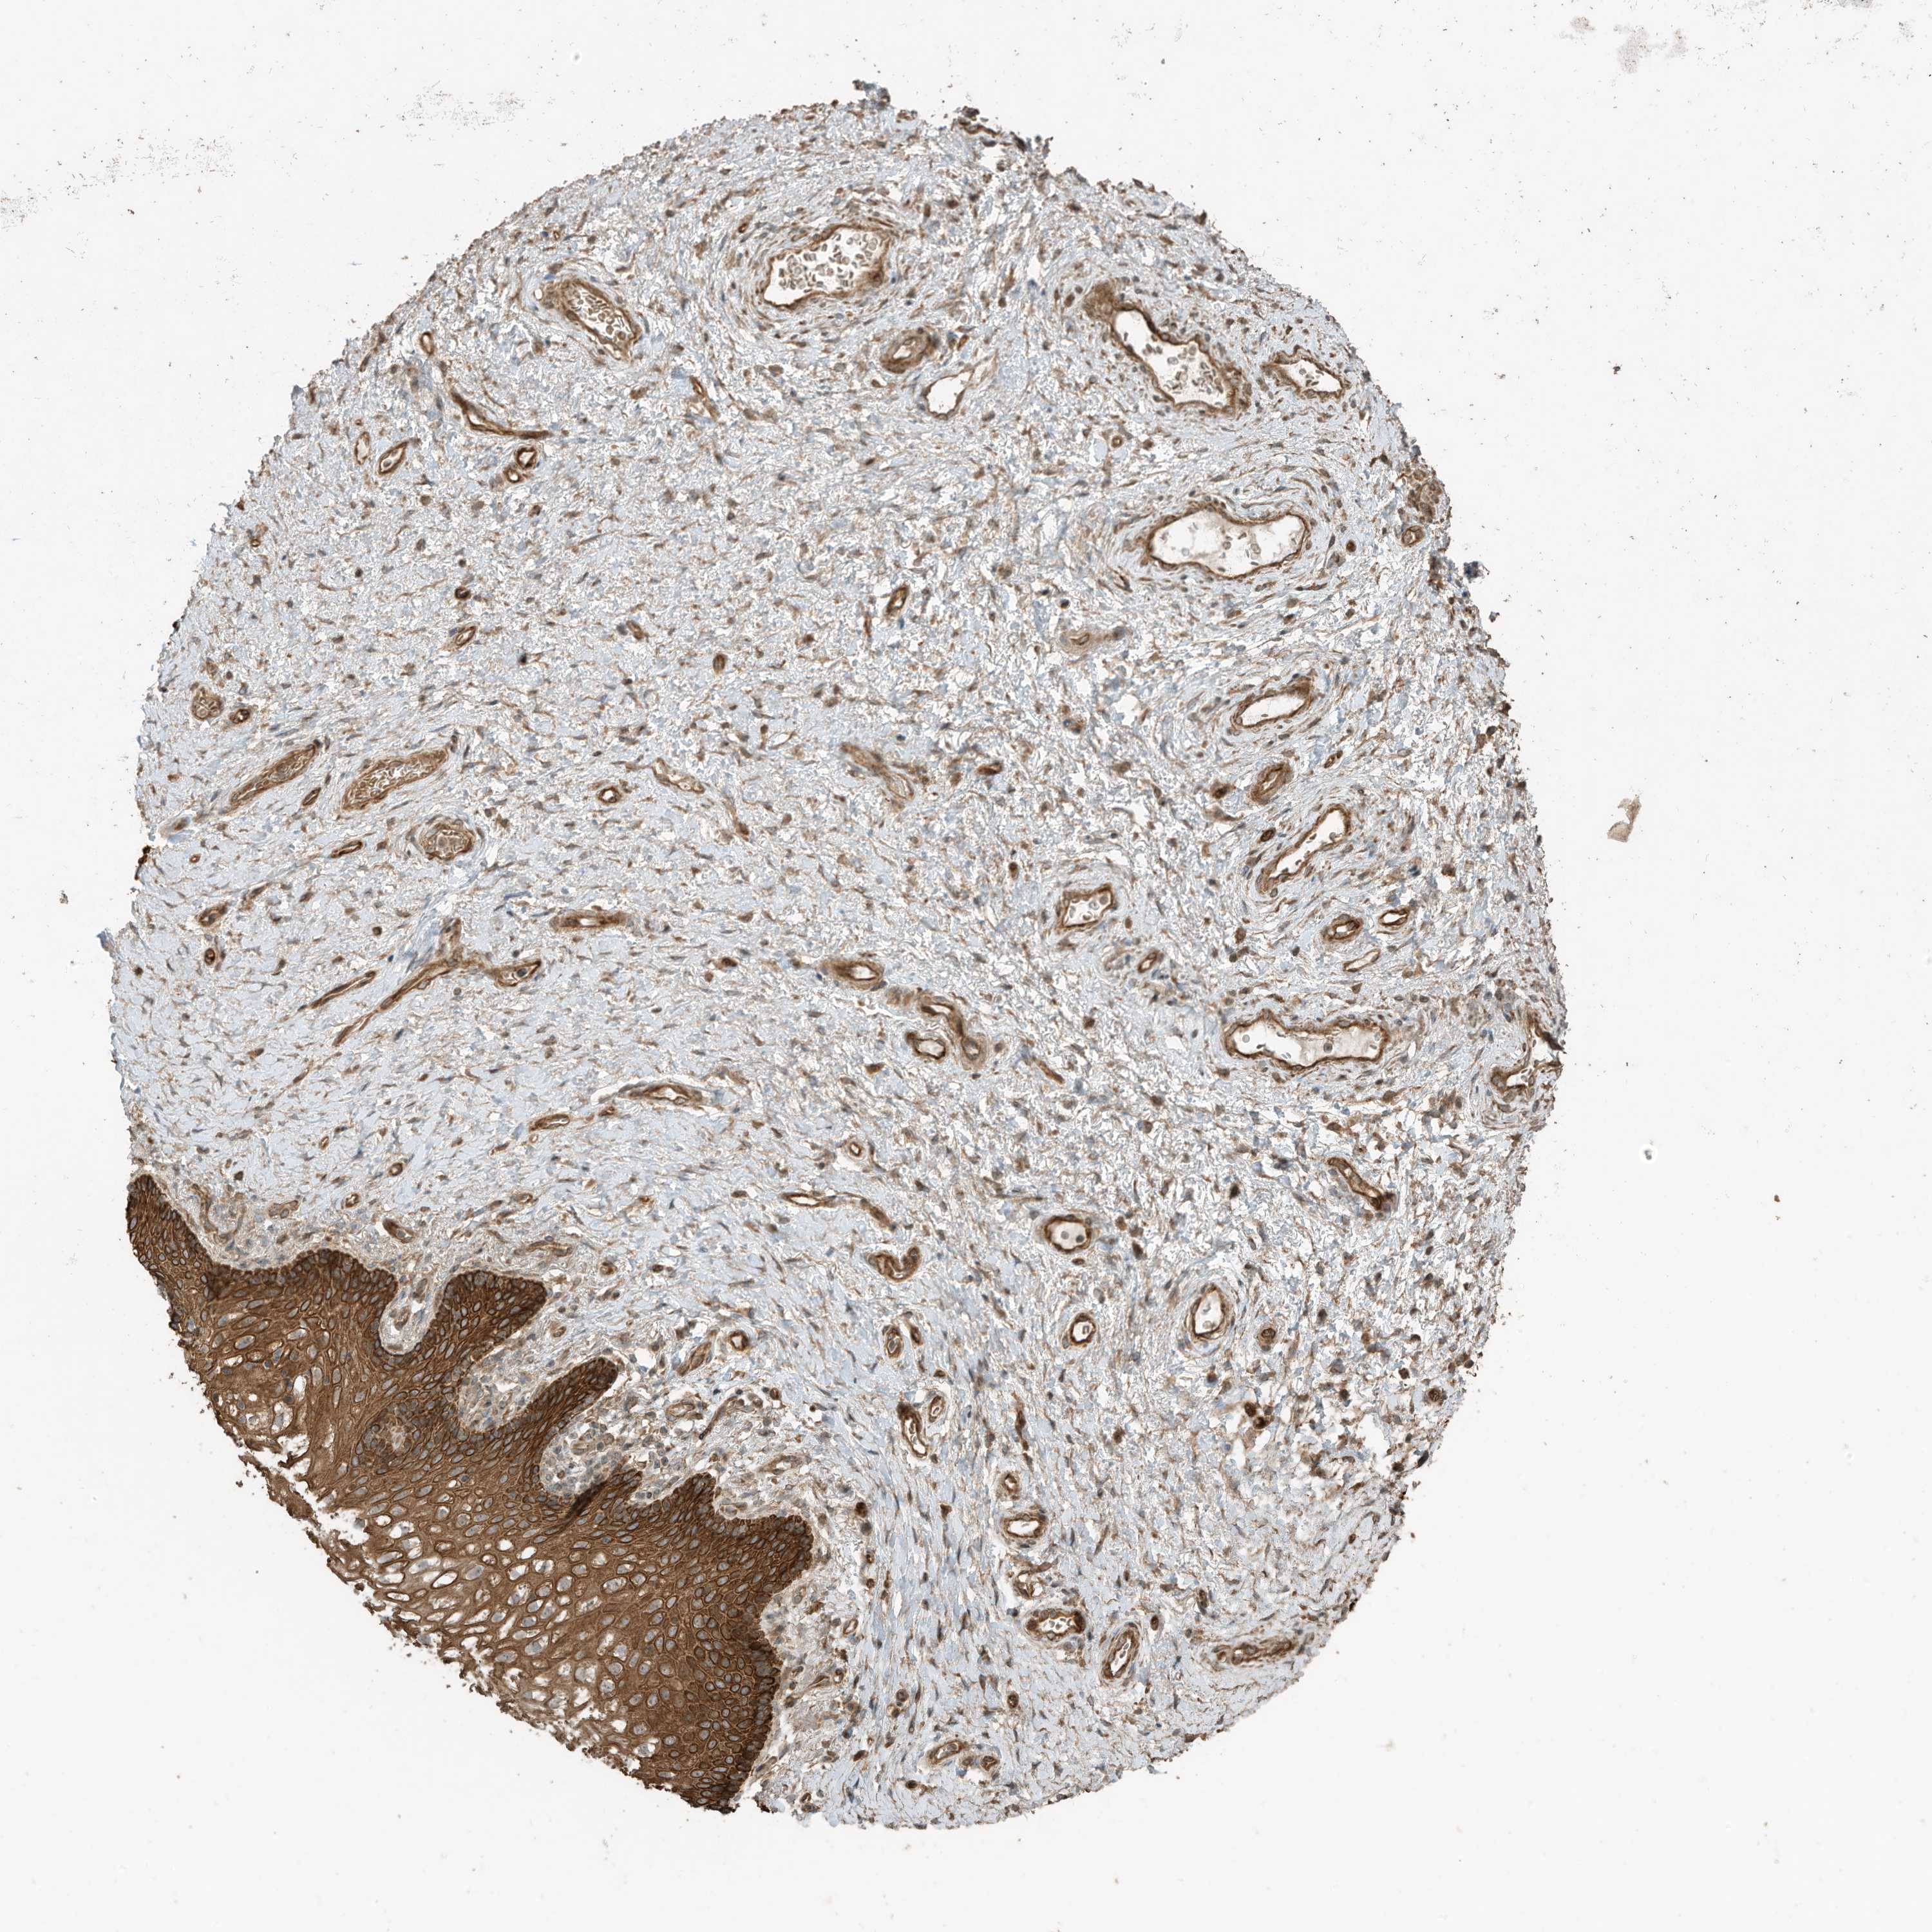

VAGINA - Antibody stainingi

Antibody staining in the annotated cell types in the current human tissue is reported as not detected, low, medium, or high, based on conventional immunohistochemistry profiling in selected tissues. This score is based on the combination of the staining intensity and fraction of stained cells.

Each image is clickable and will lead to virtual microscopy that enables deeper exploration of all samples and also displays staining intensity scores, fraction scores and subcellular localization as well as patient and tissue information for each sample.

Antibody HPA023631Antibody HPA023635

Squamous epithelial cells HighNot detected